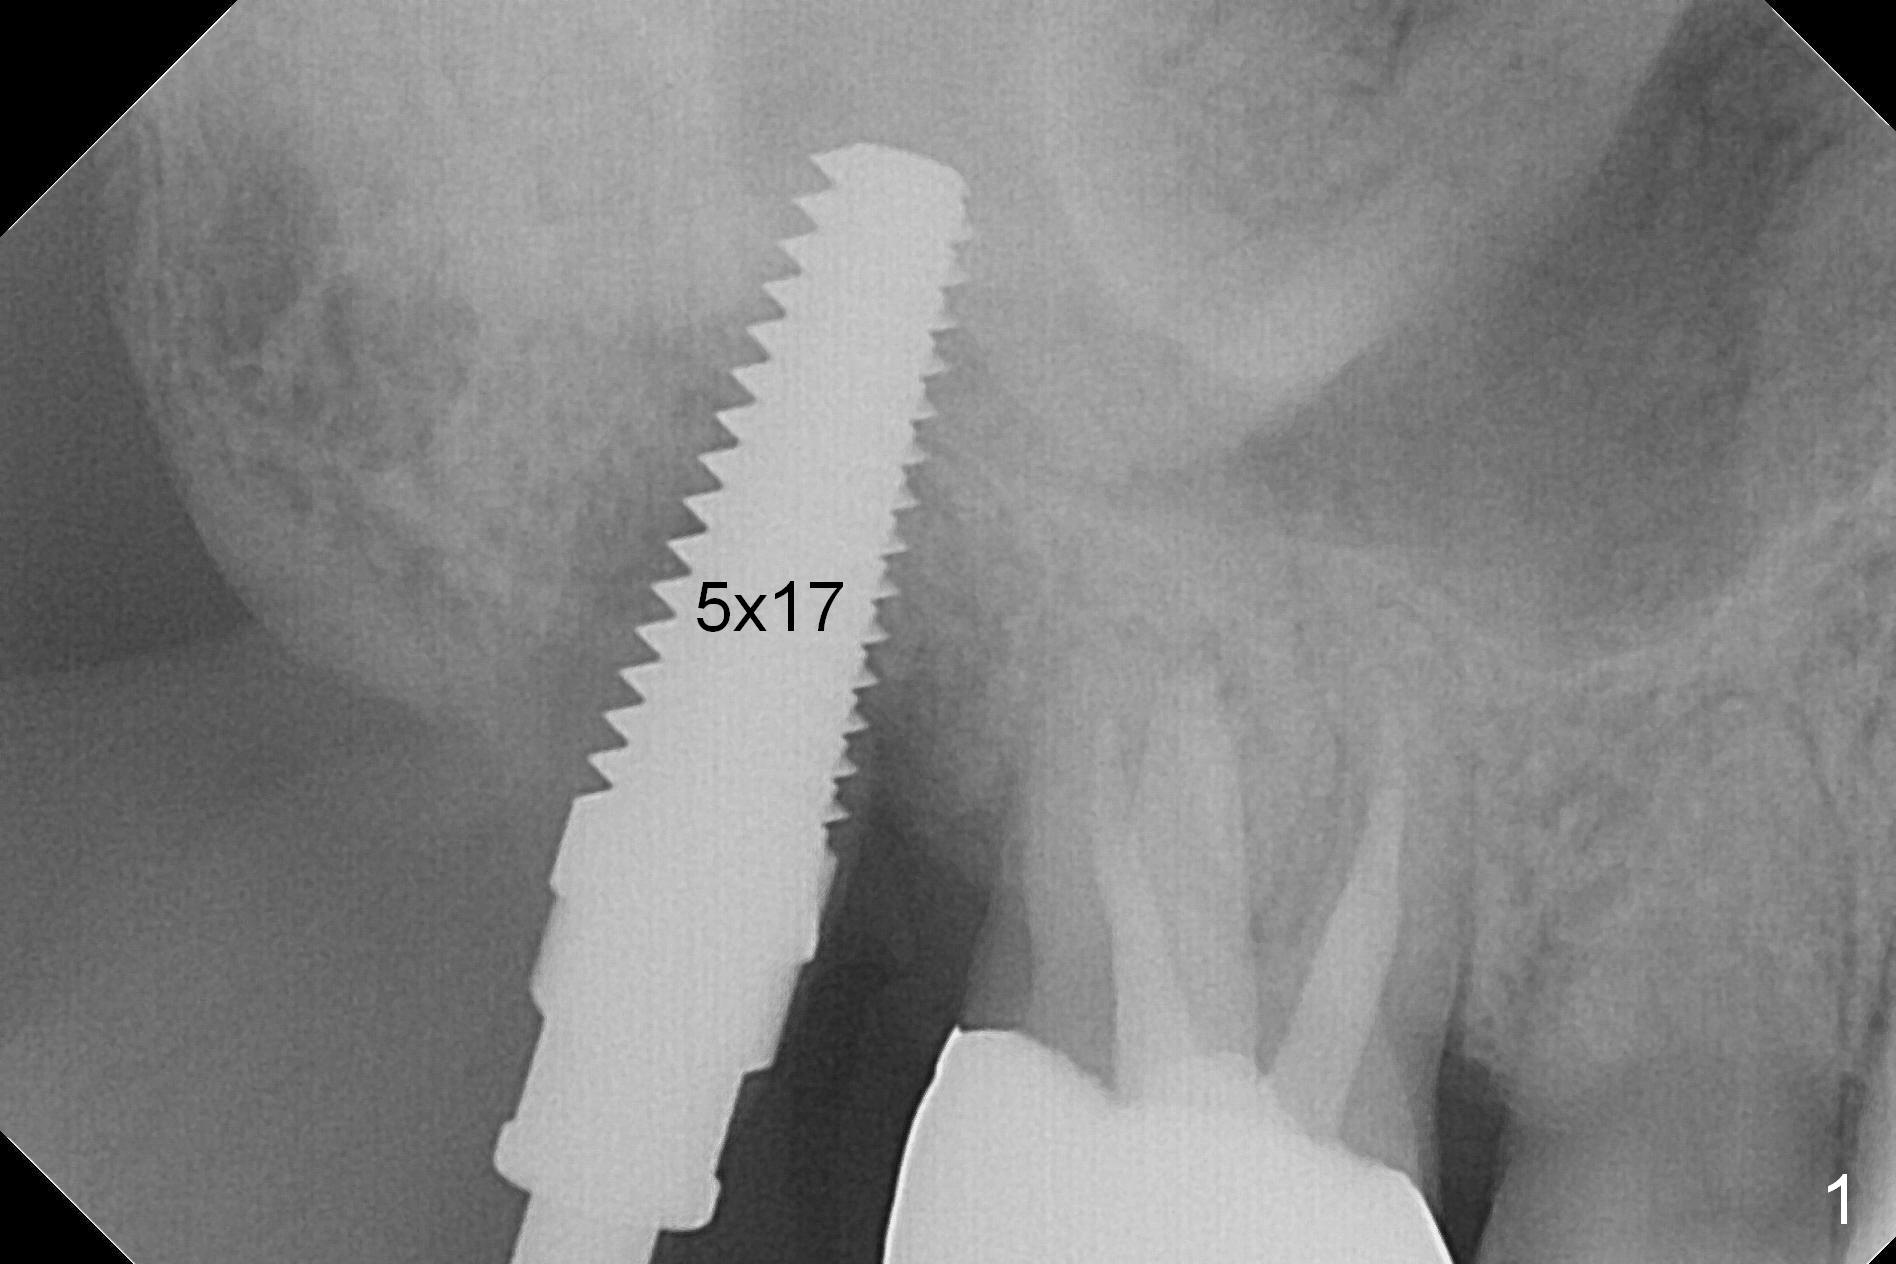

The tooth #2 is found fractured at extraction. The fused buccal (B) socket is deeper than the palatal (P) one (Fig. A * (S: sinus)); the buccal wall is low. The osteotomy is initiated in the buccal slope of the septum with Magic Expanders (3-4.8 mm, Fig. B (red)), followed by Tatum tapered tap drills (4.5-7 mm, Fig. C (green); Fig.1 (5 mm)). As the diameter of the tap drills increases, the osteotomy is shifting buccally, while larger taps are apparently losing stability. Lindamann bur is used to remove the palatal bone (Fig. D (pink) and move the osteotomy palatally (Fig. E). Because of bone height discrepancy, a 7x14 mm tissue-level implant tilts slightly buccally in the coronal end (Fig. F; Fig.2). Insertion torque is between 35 and 40 Ncm. A piece of PRF membrane and allograft is placed into the sinus prior to implantation. Following 6x3 mm abutment placement, more of allograft/Osteogen is placed in the remaining buccal and palatal sockets. A simplified provisional is applied around the implant/abutment for bone graft and collagen membrane retention.